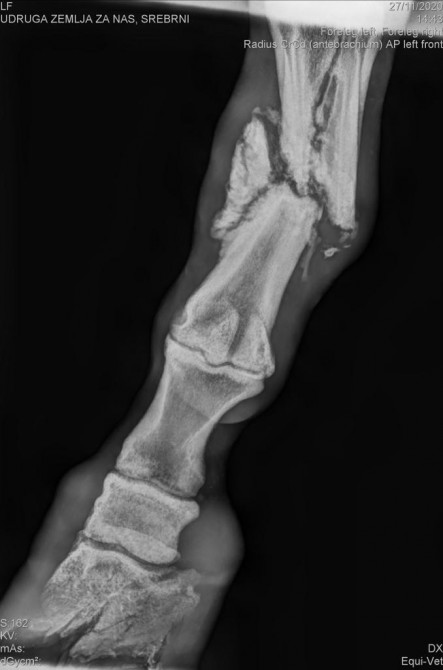

"U samom početku smo vas zamolile da nam pomognete prikupiti novce za RTG, kojim smo trebale saznati koje su opcije moguće. Ta akcija je prošla više nego uspješno i u petak 27.11. došao je Dr. Csik iz Zagreba i napravio RTG. Nakon toga, slike su slane u Beč Dr. Karstenu Veldeu, kolegi Dr. Csika koji je stručnjak za konje i ima dugogodišnje iskustvo kod takvih prijeloma na tamošnjem Veterinarskom sveučilištu. Uspostavile smo kontakt s doktorom Karstenom koji je jako optimističan oko operacije, ali i realan u smislu hitnosti i potencijalnih komplikacija", opisuju iz udruge.